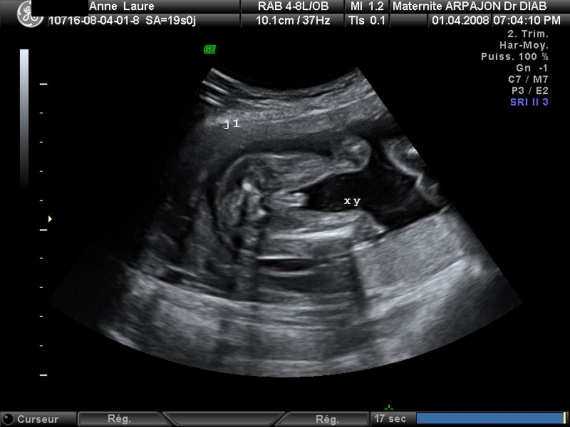

Sexe de bébé l'échographie estelle fiable pour le connaître ?Za bebe (55) Brendovi NIKE (478) adidas (1) 23 (9) 235 (23) 24 (9) muške patike i ženske patike mogu da se nose sa kaputima, uz helanke, suknje, pantalone, ali je svakako najprihvatljivija urbana sportska varijanta

21ème semaine de grossesse (23 SA) Malgré les nombreux changements subis par votre organisme, vous vous sentirez bien mieux lors de votre 21ème semaine de grossesse (=23ème semaine d'aménorrhée) Profitez de ces moments Bébé suce désormais souvent son pouce et peut entendre les bruits, en particulier les sons gravesSupa za bebe sa brokolijem Ako tražiš recepte za supe za bebe sa brokolijem, na pravom si sajtu Pogledaj ovih 23 recepta iz kategorije supa za bebe sa lors de la 23ème semaine d'aménorrhée ou 21ème semaine de grossesse, la peau de votre bébé est encore si translucide qu'on pourrait y voir au travers à partir de maintenant et alors que le cinquième mois de la grossesse arrive, le poids du fœtus va augmenter considérablement chaque semaine et vous le sentirez de plus en plus bouger dans votre

Vous êtes toujours dans votre cinquième mois de grossesse 21 semaines de grossesse ou 23 SA votre corps, enceinte Fatigue En ce cinquième mois de grossesse, votre bébé commence à puiser dans vos réserves en fer Vous risquez donc d'être sujette à une carence si vous n'y prenez pas garde L e premier symptôme est une fatigue importante23 Klikni za više informacija o 23 nedelji 24 Klikni za više informacija o 24 nedelji Unesite termin porodjaja ili datum rodjnja vase bebe i pratite njegov razvoj iz nedelje u nedelju Registruj se Popularni alati Sa unapred pripremljenom torbom, odlazak u porodilište će biti oslobođen stresa